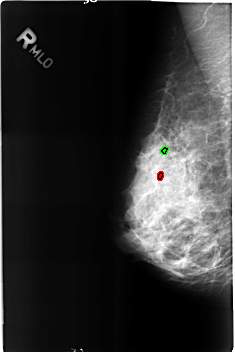

B_3162_1.RIGHT_MLO

FILE: B_3162_1.RIGHT_MLO.OVERLAY

TOTAL_ABNORMALITIES 2

ABNORMALITY 1

LESION_TYPE CALCIFICATION TYPE ROUND_AND_REGULAR-LUCENT_CENTERED DISTRIBUTION N/A

ASSESSMENT 2

SUBTLETY 4

PATHOLOGY BENIGN

TOTAL_OUTLINES 1

BOUNDARY

ABNORMALITY 2